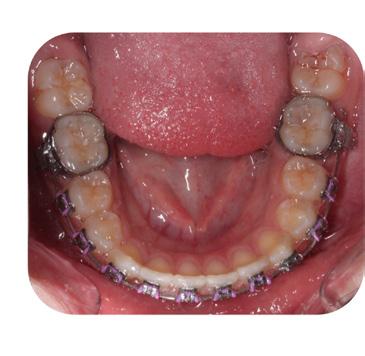

Please view the post-treatment images at the time of insertion of the retainers (Figure 13 – A, B, C. D, E, F, G, H, I, J, K, L).

FIG. 13E: Post-treatment, mandible, occlusal view

FIG. 13F: Maxillary QCM retainer